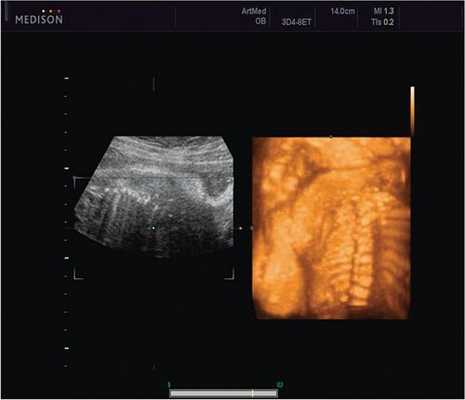

Клиническое наблюдение 1

Пациентка К., 26 лет, обратилась в клинику в 23 нед беременности. Беременность первая. Исследование проводилось на аппарате Accuvix-XQ (Samsung Medison) с использованием режима поверхностной объемной реконструкции 3D/4D. Показатели фетометрии полностью соответствовали сроку беременности. В процессе сканирования позвоночника во фронтальной и сагиттальной плоскостях выявлена угловая деформация позвоночника в грудном отделе, протяженностью около трех позвонков. В поперечной плоскости сканирования нарушения структур и целостности тканей не было обнаружено. В режиме 3D/4D реконструкции было выявлено асимметричное расхождение ребер правой и левой стороны грудной клетки (рис. 4).

Рис. 4. Эхографическая картина асимметрии ребер в режиме 3D реконструкции.

Ребра левой стороны были сближены, межреберные промежутки уменьшены по сравнению с противоположной стороной (рис. 5, 6). Другой патологии у плода не было выявлено. Заподозрен врожденный сколиоз, основой которого является наличие боковых полупозвонков (hemivertebrae) или боковых клиновидных позвонков. В 26 нед ультразвуковая картина сохранялась. При проведении трехмерной эхографии получено отчетливое изображение асимметрии реберных дуг и сколиотическая деформация позвоночника.